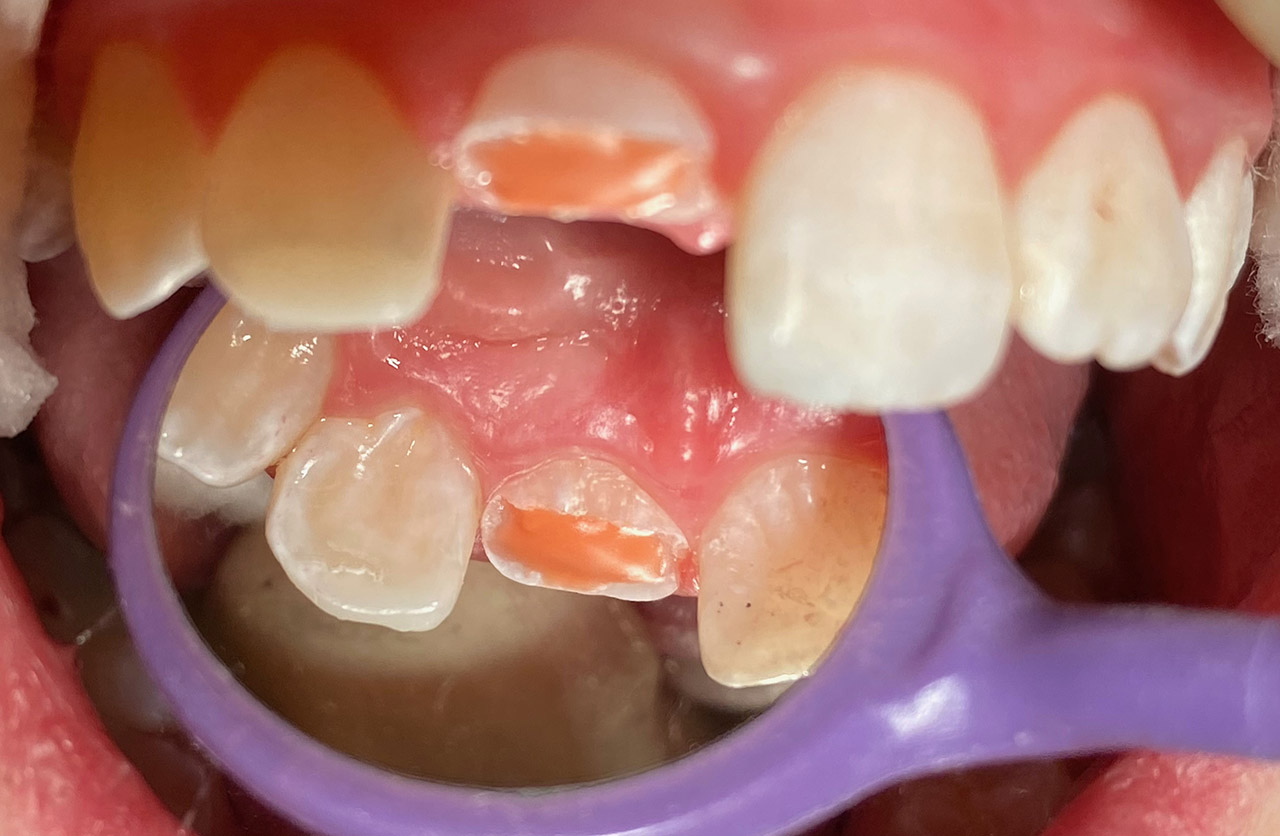

Traumatologie und Endodontie:

Nach Unfall/Sturz mittlerer Schneidezahn auf Gingivaniveau abgebrochen, Pulpa weit eröffnet, beide Nachbarzähne ebenfalls frakturiert.

Erstversorgung: Pulpektomie der Kronenpulpa, MTA, provisorischer Verschluß mit rosa Glasionomerfüllung.

Wiederaufbau der Nachbarzähne mit mitgebrachten (plus 1 Stein) Zahnstücken mit Kunststoff ergänzt und adhäsiv verklebt.

2. Schritt nach Aushärtung von MTA: Entfernung der Kronenpulpa im Bruchstück zur Vermeidung von Verfärbung, Füllung mit Kunststoff.

Adhäsives zementieren des abgebrochenen Zahnstücks.